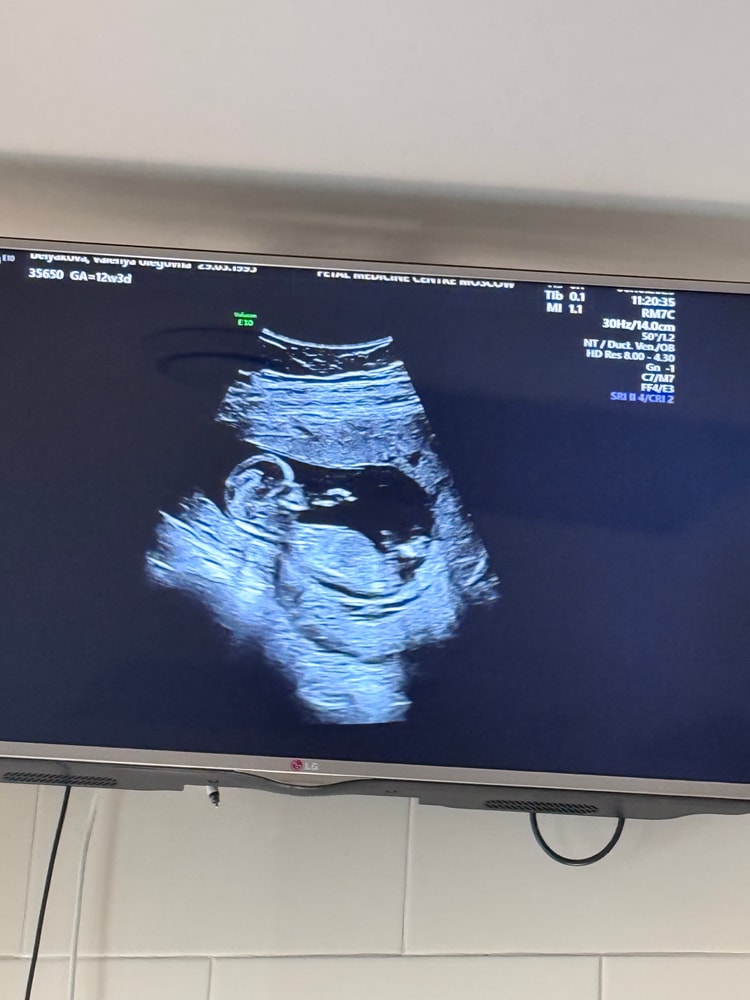

Мальчик ли

посмотрите

по крови мальчик пришел

По узи 11,1 неделя

по М 10,3 недель